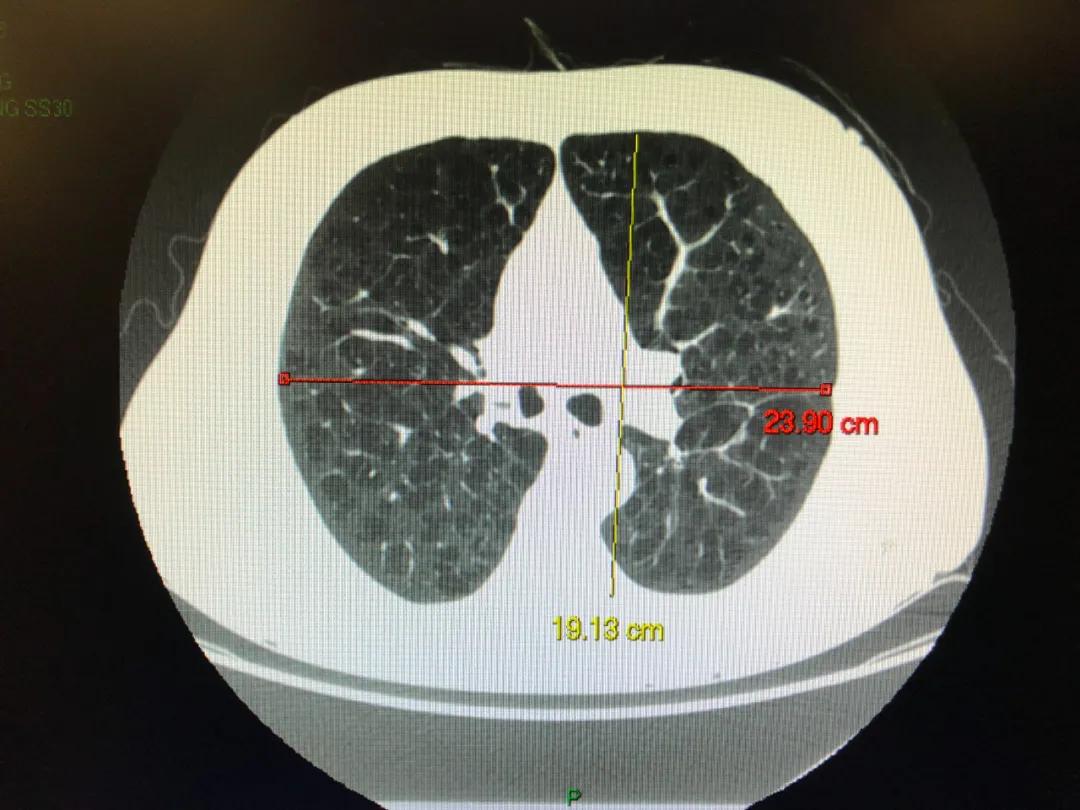

图为该患者胸部CT特殊成像方式, 图中红色部分显示双肺多发不均匀性肺气肿

这位患者是重度肺气肿伴有过度充气。就像气球丧失了弹性,肺气肿就是肺泡丧失了弹性。正常情况下,人体吸气时肺泡变大,呼气时肺泡变瘪,一吸一呼间把新鲜氧气吸进来,把二氧化碳废气排出去。

该患者近3年憋气症状加重,就是跟他的肺气肿有关系。通过该患者的胸部CT也可以看出患者是不均匀型的肺气肿,也就是不同肺叶的肺气肿轻重不一。